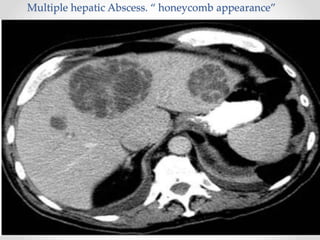

Pyogenic Abscess

• Most common abscess seen in the U.S .

• 40%  Monomicrobial.

• 40%  Polymicrobial.

• 20%  Negative Culture.

• Commenst are Gram negative : E.coli (70%) , klibseila

proteus.

• Most common liver abscess in the U.S .

• In patients with endocarditis and infected indwelling

catheters, Staphylococcus and Streptococcus species are

more commonly found.

• Treatment include correction of the underlying cause and

IV antibiotic therapy (8 weeks ).

Multiple hepatic Abscess. “ honeycomb appearance”